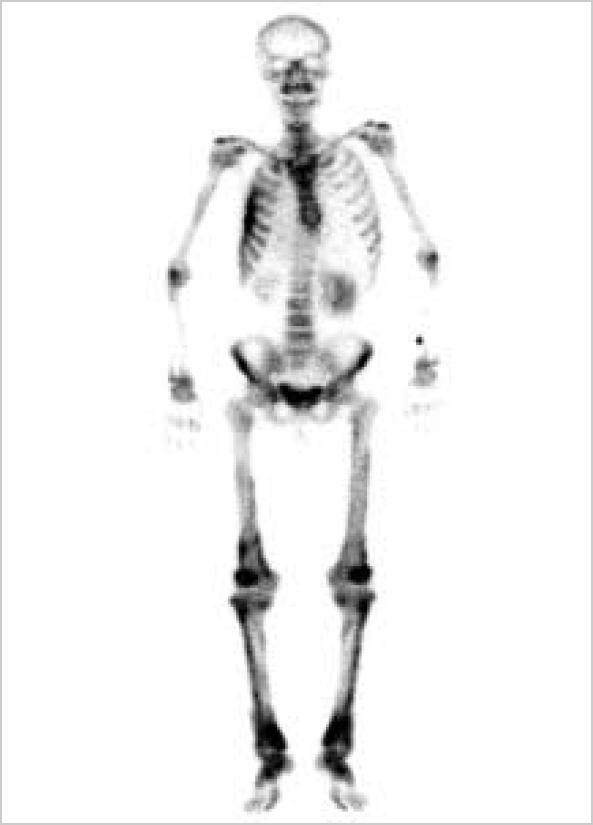

Epithelioid hemangioendothelioma is a rare vascular tumor, which occurs in the lung, liver, bone, and soft tissue. Hypertrophic osteoarthropathy is a syndrome characterized by subperiosteal new bone formation, joint effusion and clubbing, and may be associated with cyanotic heart disease, chronic pulmonary disease, liver disease, and other miscellaneous diseases. The activation of endothelium and platelets has been suggested to be involved in the development of hypertrophic osteoarthropathy. We report a rare case of hypertrophic osteoarthropathy, which developed in association with hepatic epithelioid hemangioendothelioma with pulmonary metastasis. We also discuss the role of vascular endothelial growth factor in its pathogenesis.

上皮样血管内皮瘤是一种罕见的血管肿瘤,可发生于肺、肝、骨和软组织。肥大性骨关节病是一种以骨膜下新骨形成、关节积液和杵状指为特征的综合征,可能与紫绀型心脏病、慢性肺部疾病、肝脏疾病及其他杂病有关。内皮细胞和血小板的激活被认为与肥大性骨关节病的发生有关。我们报告一例罕见的肥大性骨关节病病例,其与肝上皮样血管内皮瘤伴肺转移相关。我们还讨论了血管内皮生长因子在其发病机制中的作用。